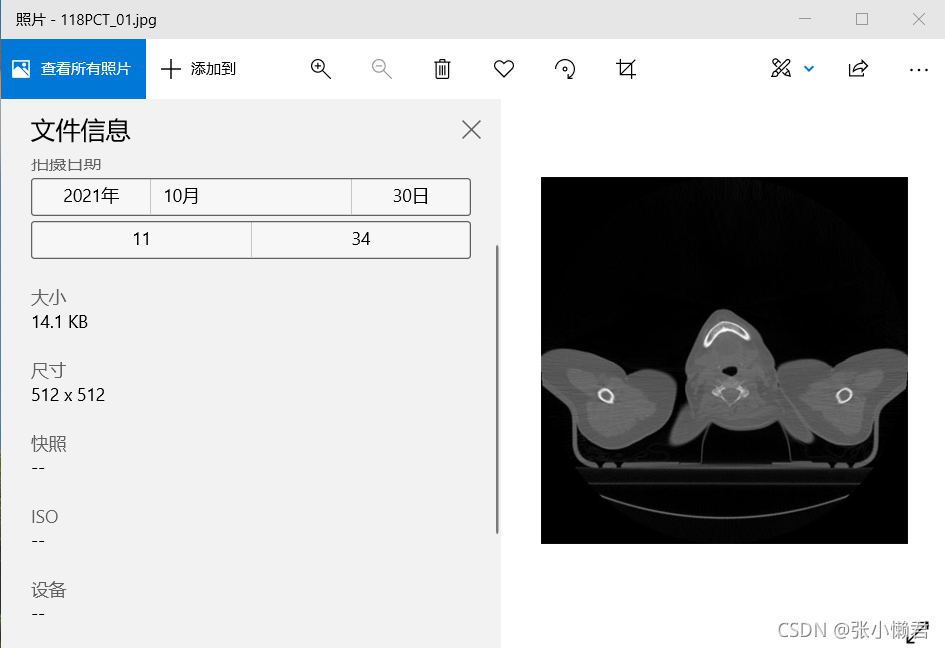

imageio.imsave("118PCT_01.JPG", img_arr)将DICOM格式图像转换为JPG格式的思路就是:

①从DICOM文件中读出图像数据矩阵ima_arr(512*512,256*256)

②imageio.imsave("118PCT_01.JPG", img_arr)将矩阵img_arr保存成灰度图像

鉴别:

#imageio.imsave()函数将从DICOM文件中读取到的512*512的矩阵转换成--->单通道的灰度图像(512,512)

import imageio

dcm = pydicom.read_file("118PCT_01.dcm")

img_arr = dcm.pixel_array

imageio.imsave("118PCT_01.JPG", img_arr)

#512*512矩阵--->三通道图像(512,512,3)

import matplotlib.pyplot as plt

dcm = pydicom.read_file("118PCT_01.dcm")

img_arr = dcm.pixel_array

jpgname = "118PCT_01.jpg"

plt.figure(figsize=(8,8),dpi=64) # 设置图像分辨率位512*512

plt.imshow(img_arr,'Greys_r')

plt.title("UID:{}".format(uid))

plt.savefig(jpgname)

plt.close()